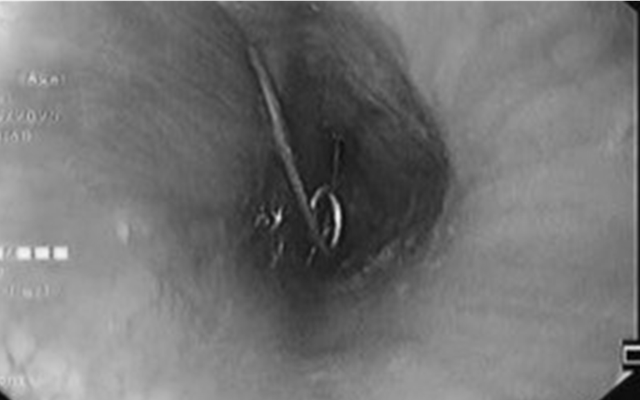

Cháu bé 1 tuổi nuốt kim băng đã bung đầu nhọn ghim vào thành thực quản. Ảnh: Bệnh viện cung cấp.

Tại khoa Cấp cứu, các bác sĩ tiến hành thăm khám và nội soi khẩn cấp. Kết quả cho thấy cây kim băng đã bung ra hình chữ L, đầu nhọn ghim vào thành thực quản gây nguy cơ thủng, xuất huyết và nhiễm trùng nặng. Đây là tình huống đòi hỏi xử lý nhanh chóng, chính xác và cẩn trọng để bảo vệ tính mạng và sức khỏe của bệnh nhi.

Tiếp đó, ê-kíp liên chuyên khoa gồm Tiêu hóa - Tai Mũi Họng - Ngoại khoa, Bệnh viện Nhi đồng 2 TpHCM được huy động để hội chẩn và triển khai phương án can thiệp. Sau quá trình xử lý nội soi tỉ mỉ, các bác sĩ đã lấy được dị vật mà không cần phẫu thuật mở. Nhờ sự phối hợp nhịp nhàng giữa các chuyên khoa, ca cấp cứu đã diễn ra an toàn, bé được cứu khỏi một tình huống nguy hiểm.